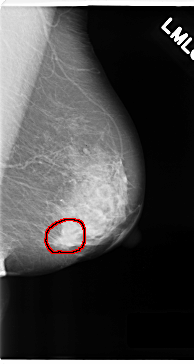

C_0180_1.RIGHT_MLO

FILE: C_0180_1.LEFT_MLO.OVERLAY

TOTAL_ABNORMALITIES 1

ABNORMALITY 1

LESION_TYPE MASS SHAPE LOBULATED MARGINS SPICULATED

ASSESSMENT 5

SUBTLETY 5

PATHOLOGY MALIGNANT

TOTAL_OUTLINES 1

BOUNDARY